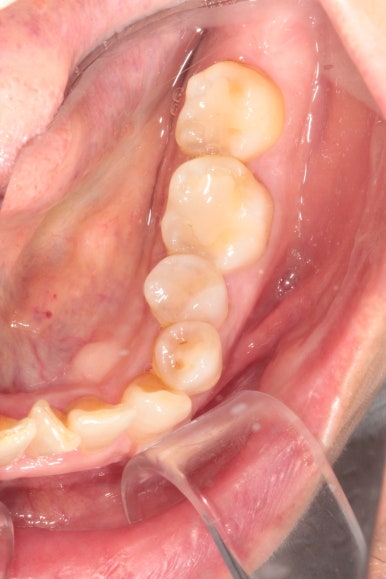

교정 시작하고 6개월만에 치아배열이 다되어갑니다.

이제 정말 많이 배열이 완성되었습니다. 아래 앞니를 배열시키느라 시간이 조금 더 걸렸던 것 같아요.